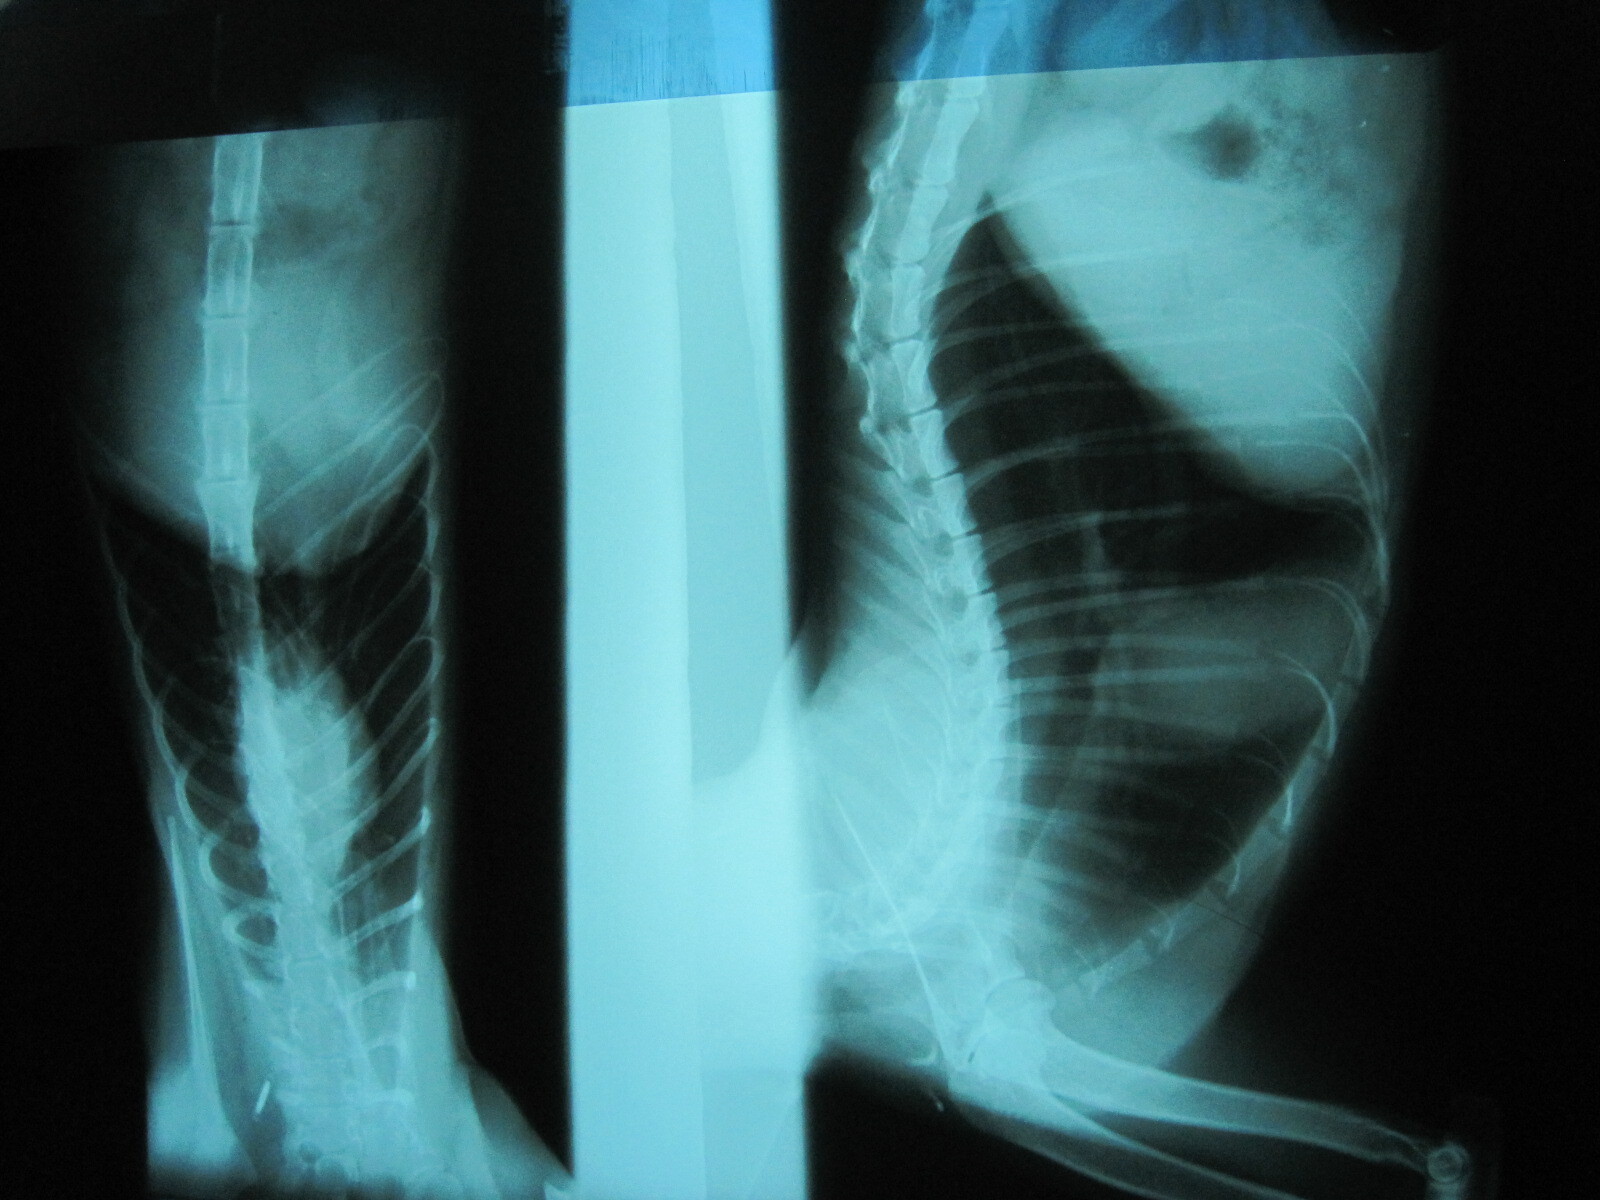

主題: 流鼻涕的小黃 引起上唇潰爛 申請者姓名: 張慧敏 花色: 申請日期: 2012-10-23 21:21:49 申請者部落格: 申請者臉書網址: 所在縣市/合作醫院: 台北市/詠欣動物醫院 治療費用: 6500元 需求人數: 8人 已結案 (2013-06-27 13:51:48) 報名人員: 謝大隻(已付款)、Amy(已付款)、Cherry Lin(已付款)、波波(已付款)、明達電子有限公司(已付款)、明達電子有限公司(已付款)、帝柳(已付款)、Michelle(已付款)、 候補人員: 動物病情說明: 小黃流了一陣子的鼻涕,最近有變瘦和食慾不好的狀況.仔細一看,發現上唇也潰爛了.照x光 幸好肺部未受感染.於是進行一陣子的醫療.目前不流鼻涕,傷口也縮小了.就先出院回家繼續調養.